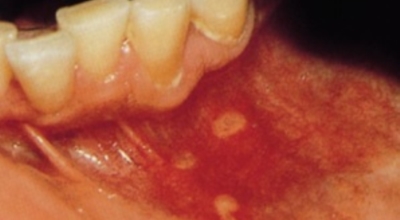

구내염 원인 - 아프타성 구내염

입안 점막이 동그랗게 패여 통증을 유발한다면, 아프타성 구내염을 의심할 수 있어요. 음식을 먹을 때마다 아픈 작은 궤양이 생겼다면, 아프타성 구내염을 의심할 수 있어요. 아프타성 구내염은 빨간색 둘레를 가진 둥근 형태의 흰색 궤양이, 얕은 깊이로 한 개 및 여러 개 생기며 통증을 동반하는 것이 특징입니다. 전 인구의 20~40%가 발병할만큼 통상적으로 나타나는 질환으로 20대, 주로 여성분들에게 많이 나타나며, 일주일 정도면 자연적으로 치유되지만 1~3개월 간격으로 빈번히 재발하는 것이 특징입니다.

까닭은 입 속 점막의 작은 상처나, 바이러스, 세균의 감염, 각별히 수면 부족이나 과로, 스트레스가 축적돼 면역력이 떨어졌을 때와, 비타민 B12 또는 엽산 결핍 시에 많이 생기 다고 알려져 있어요. 흔한 질환이니만큼 자연적으로 치유 되지만, 통증을 동반하고, 궤양의 크기가 커지거나 숫자가 늘어나기도 하기 때문에 연고나 외용제, 가글액 등을 활용해서 증상을 경감시키는 치료를 하기도 해요.